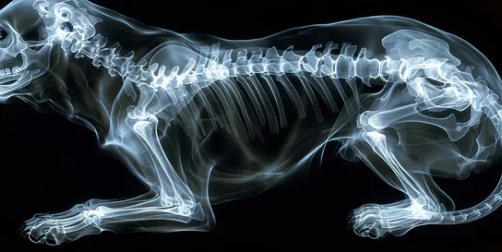

- X-ray나 CT 촬영으로 상태를 확인.